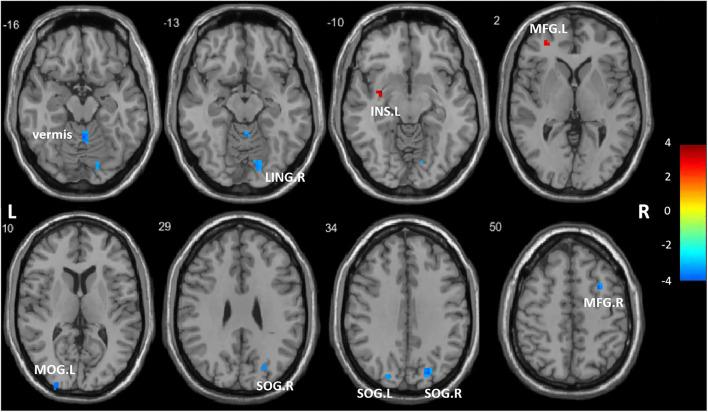

Compared with HCs, ANI patients had a significant ReHo decrease in the right lingual gyrus (LING. R), right superior occipital gyrus (SOG. R), left superior occipital gyrus (SOG. L), left middle occipital gyrus (MOG. L), right middle frontal gyrus (MFG. R), cerebellar vermis, ReHo enhancement in the left middle frontal gyrus (MFG. L), and left insula (INS L). The ANI patients showed increased FC between the LING. R and MOG. L compared to HC. For ANI patients, verbal and language scores were negatively correlated with increased mean ReHo values in the MFG.L. Increased mean ReHo values in the INS. L was positively correlated with disease duration-the mean ReHo values in the LING. R was positively correlated with the abstraction and executive function scores. Increased FC between the LING. R and MOG. L was positively correlated with verbal and language performance.

The results suggest that the visual network might be the most vulnerable area of brain function in young HIV-infected patients with ANI. The middle frontal gyrus, cerebellar vermis, and insula also play an important role in asymptomatic neurocognitive impairment. The regional homogeneity and functional connectivity of these regions have compound alterations, which may be related to the course of the disease and neurocognitive function. These neuroimaging findings will help us understand the characteristics of brain network modifications in young HIV-infected patients with ANI.